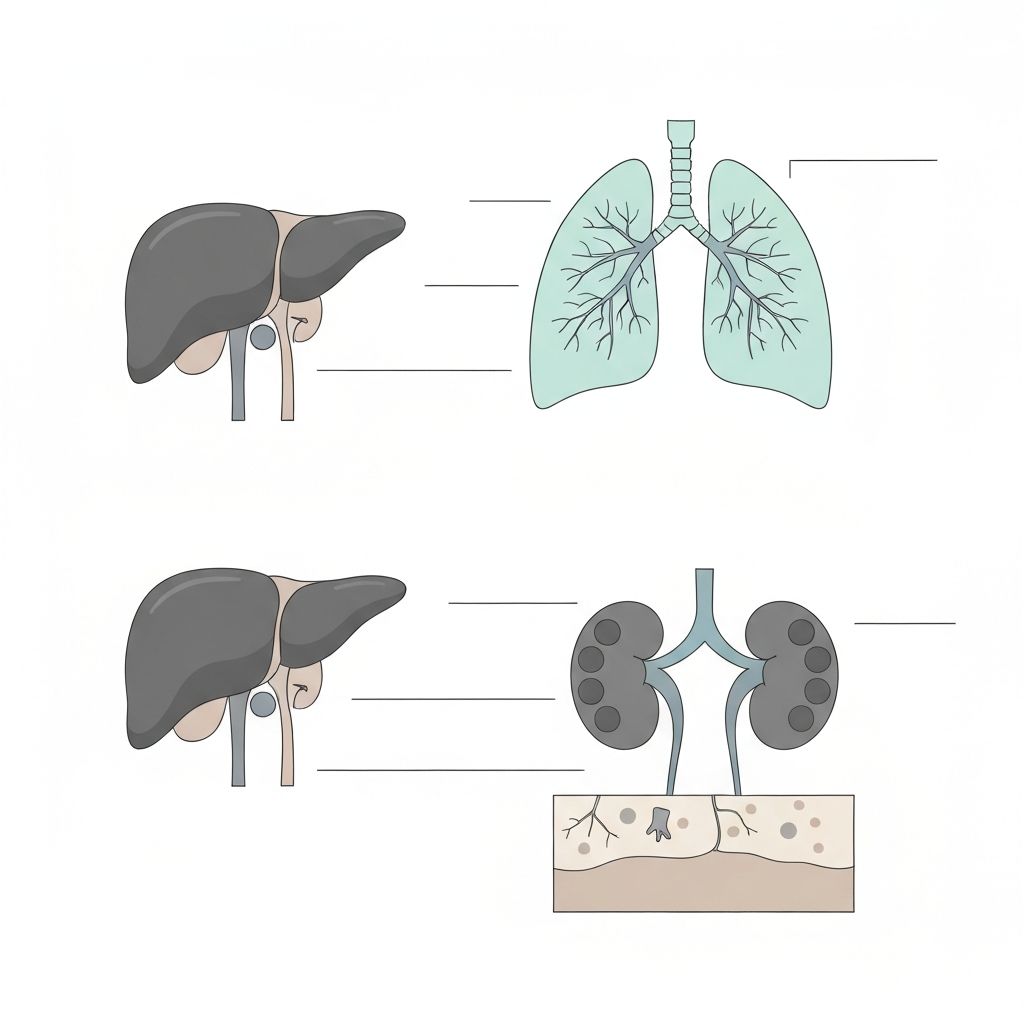

Primary Organs and Their Roles

The human body has evolved sophisticated systems to process and eliminate substances that cannot be used for energy or structural functions. These systems involve the liver, kidneys, lungs, skin, and gastrointestinal tract working in coordination.

Key Detoxification Organs

The liver is the primary organ responsible for metabolizing foreign compounds through enzymatic pathways. The kidneys filter metabolic waste from the bloodstream. The lungs eliminate volatile compounds through respiration. The skin has limited excretory function, primarily through sweat containing water-soluble compounds.

Explore Detailed Organ Function Articles

Liver Phase I and Phase II

Detailed biochemical mechanisms of cytochrome P450 and conjugation pathways.

Read the detailed physiological explanationRenal Excretion

How kidneys filter and eliminate metabolic byproducts from the bloodstream.